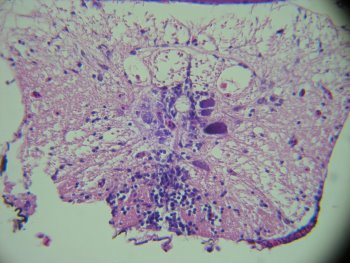

病理組織病變:最典型的特微性病變為於視網膜及腦、脊髓的神經細胞發生壞死與空泡化病變。在空泡化病灶的腦組織及視網膜細胞內可觀察到非常多的嗜鹼性質內包涵體 (inclusion body)。(Tanaka A,1998)

三級初步診斷:特徵性組織病理病變為於視網膜及腦、脊髓的神經細胞發生壞死與空泡化病變。